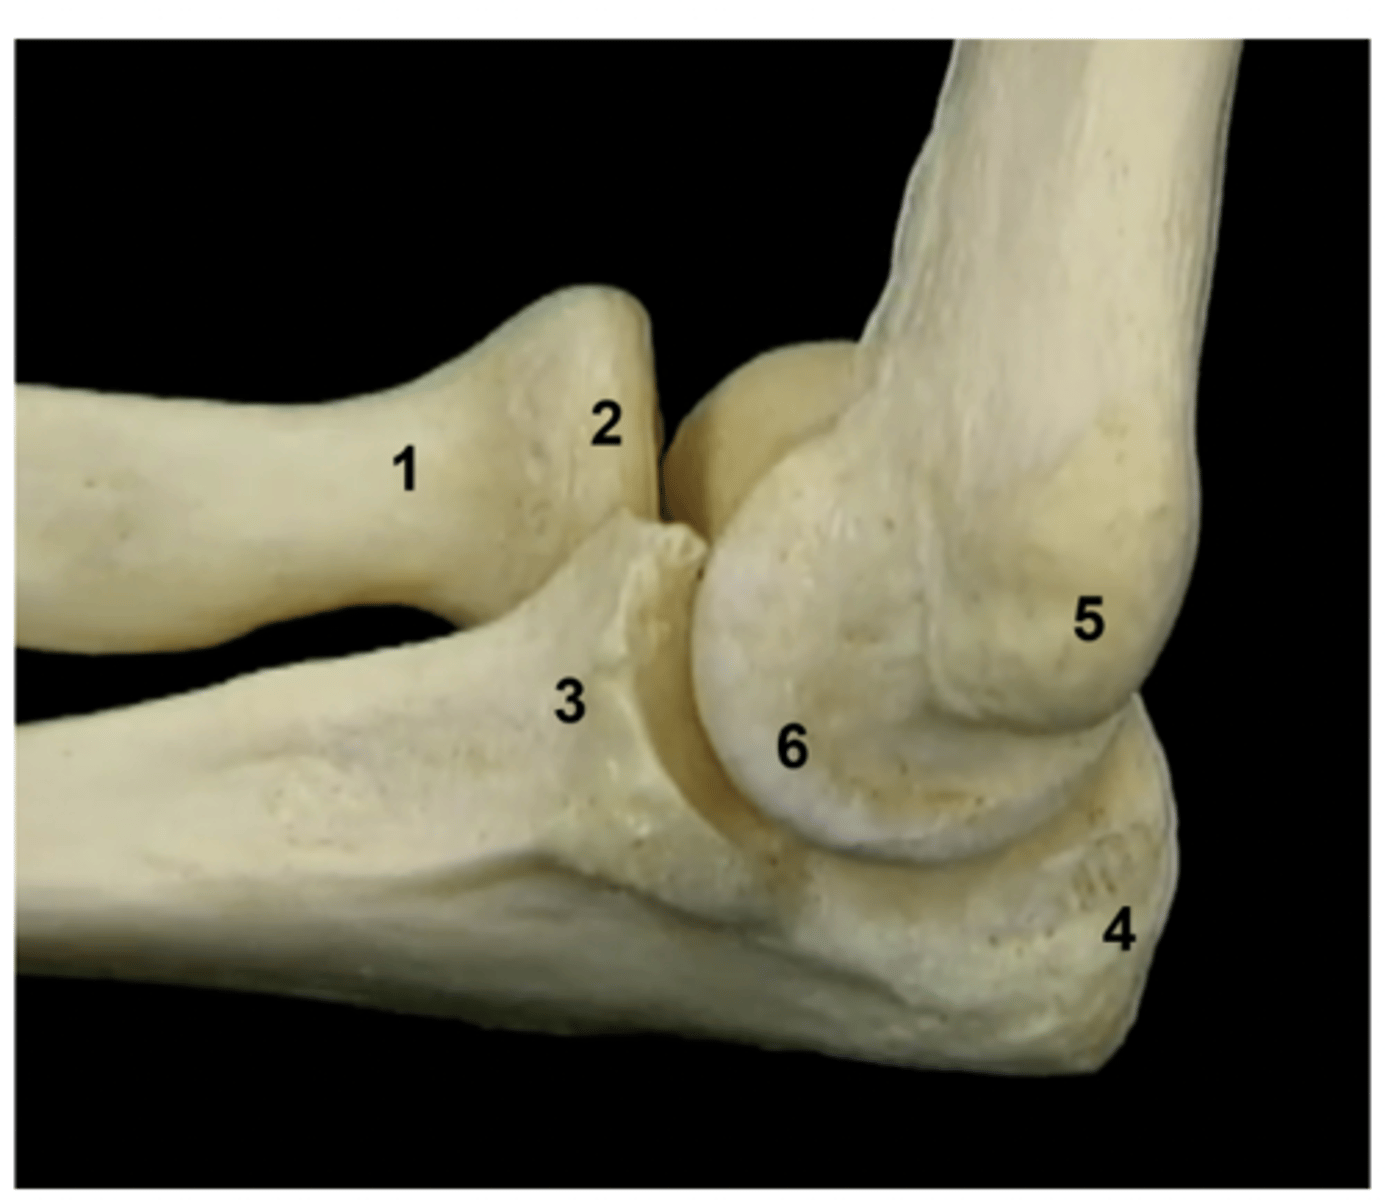

Inverse card: label the image

1. Neck of radius

2. Head of radius

3. Coronoid process

4. Olecranon

5. Medial epicondyle of humerus

6. Trochlea